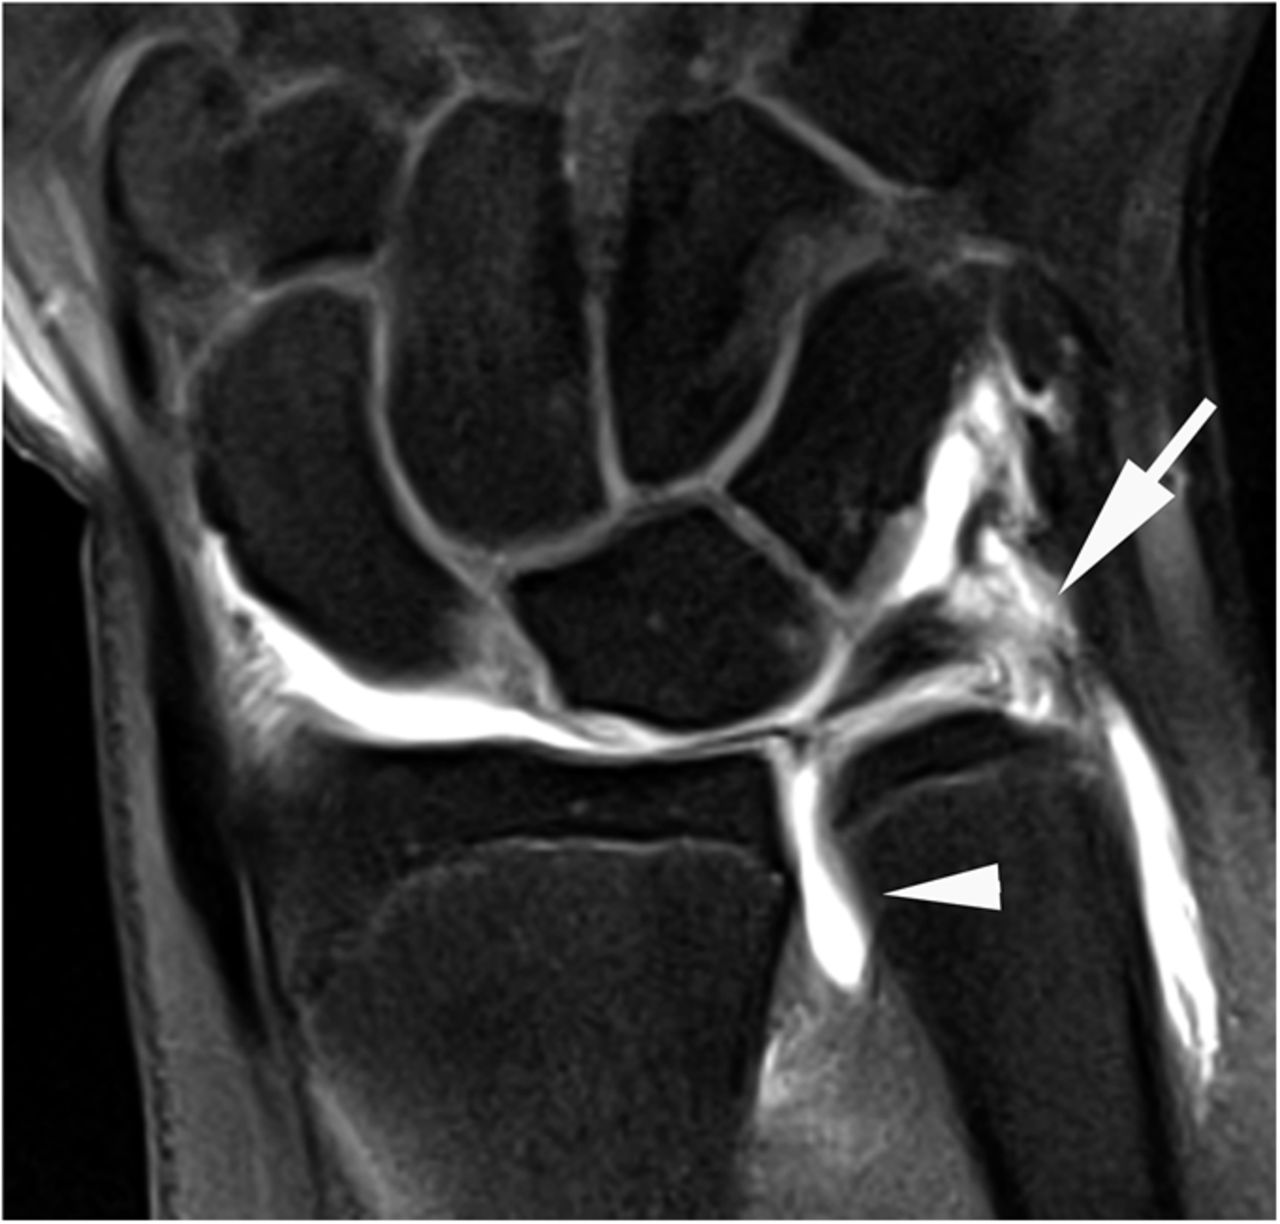

An MRI arthrogram exam is an imaging study. It is used to take detailed pictures of your joints. MRI stands for magnetic resonance imaging. This exam has 2 parts. First you will have an arthrogram and then an MRI. This 2-part exam shows more details of your joint than an MRI by itself. It will help your healthcare provider decide which treatment is best for your medical condition.

- Joints such as knee, hip, and shoulder are made up of 2 bones that fit closely together. Other tissues (cartilage, tendons, and ligaments) support and cushion your joints. An MRI arthrogram helps your doctor see small tears or other problems in these tissues. The results of this exam will help guide your treatment. It will also help your doctor keep track of problems in your joint.

- When the area is numb, a needle will be placed into your joint space. A fluoroscope will be used to guide the needle.

- When the needle is in the correct place, contrast will be injected. Your joint may feel “full,” or you may feel some pressure in the joint.

- X-ray images will then be taken.